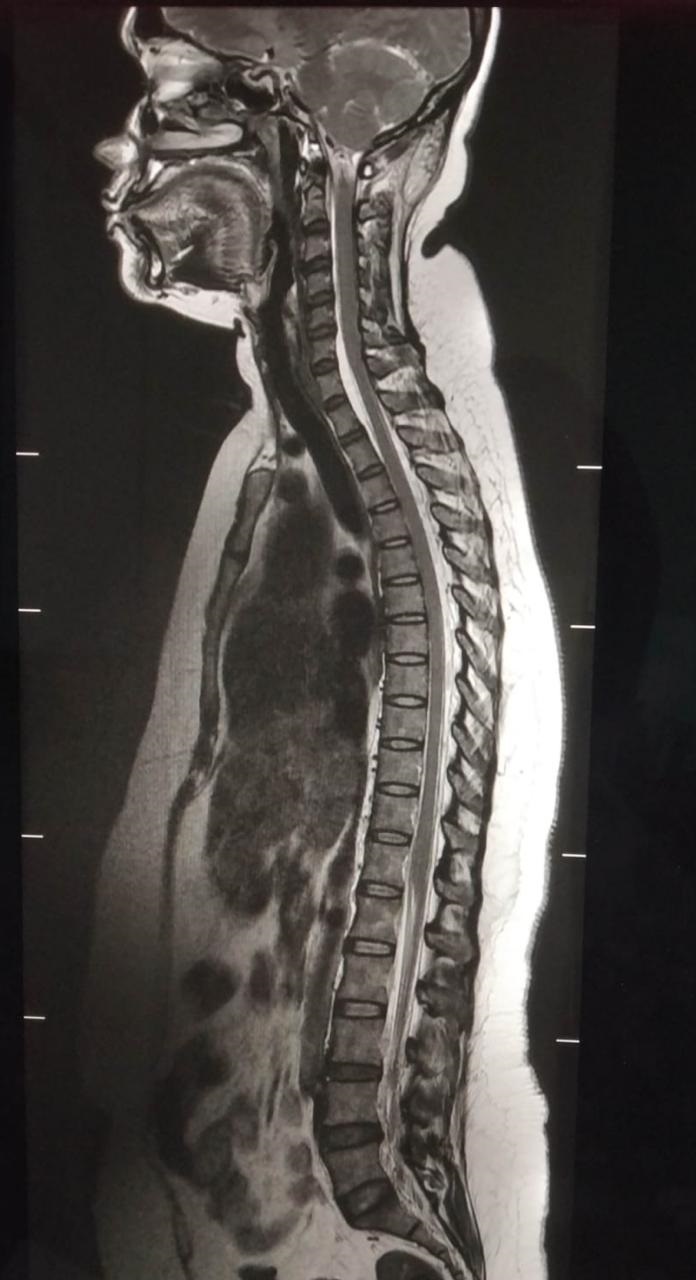

Click Here to View 2nd X-Ray Image